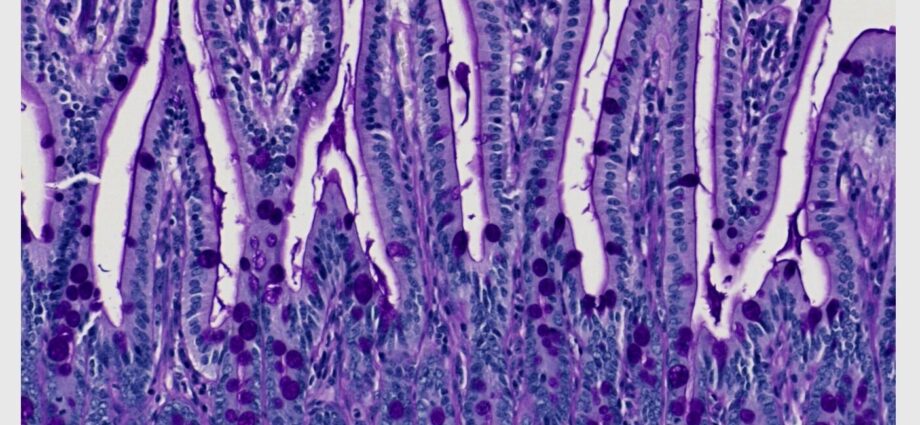

Foto Credit: Charles Ng